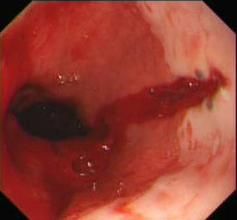

2.病理及分期撕裂部位大多數在食管末端或跨越食管胃連線部,多為線形單處撕裂,但亦有2處甚至多處撕裂者,撕裂多在黏膜皺襞間溝內。據一組224例Mallory-Weiss綜合徵報告中83%撕裂位於食管胃連線部的小彎側(圖1)。早期可見有活動性出血,或有血凝塊或纖維素塊覆蓋,以後甚至可形成淺表潰瘍本病病理上可分為4期:

酗酒、妊娠消化性潰瘍、肝硬化、腸梗阻、停服抗酸藥或食物中毒病人在嘔吐後出現上消化道出血症狀時應考慮本病的可能應在發病後24h內行胃鏡檢查。鏡下見胃食管結合部黏膜有縱行撕裂傷,或雖無明顯食管及胃黏膜損傷,但有出血來自食管-胃結合部即可確診。

賁門黏膜撕裂綜合徵1.胃鏡檢查Mallory-Weiss病變多位於食管-胃結合部,因此胃鏡檢查診斷價值優於食管鏡檢查。

Millet和Hirschowitz(1970)報導的23例Mallory-Weiss綜合徵中,19例經胃鏡檢查而確診。其中12例在內鏡下可見胃食管結合部黏膜有縱行撕裂傷,占55%;7例(30%)在內鏡下看不到食管及胃黏膜有明顯損傷,但仍然可見出血來自食管-胃結合部;3例在做胃鏡檢查時因胃內充滿血液,檢查不滿意,無法作出診斷;1例未做胃鏡檢查手術探查時發現食管下段黏膜撕裂並發出血。由此可見Miller和Hirschowitz報導的23例:Mallory-Weiss綜合徵中,85%(19/23)都是經胃鏡檢查後才作出診斷的。胃鏡檢查對這一綜合徵的診斷具有其他檢查不能代替的診斷價值,只要無禁忌證都應首先做胃鏡檢查。